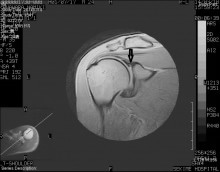

高校3年生男子、小中高とキャッチャー、野球での肩の後方の痛みで来院されました

後方の痛みは以前からあり今までケアしたことがあまり無く今回は痛みが酷いため来院

全身細身で筋肉量は少ない後方から見てみると肩甲骨が後方へ突出しやや翼状肩甲が見られました。

筋力が無く肩甲帯が後方へ偏移し、2ND MERでの疼痛強いためインターナルインピンジしているかと仮定し治療しています。

ベネット損傷(関節窩後下方の骨棘、関節唇、関節包の損傷)もインナー、アウターともに弱いため併発しているかもしれません。

こういったケースになるまで放置すると静的、動的機能の両面での向上が必要となり治療にも時間がかかります。

違和感などがある場合は早く受診するようにしましょう。